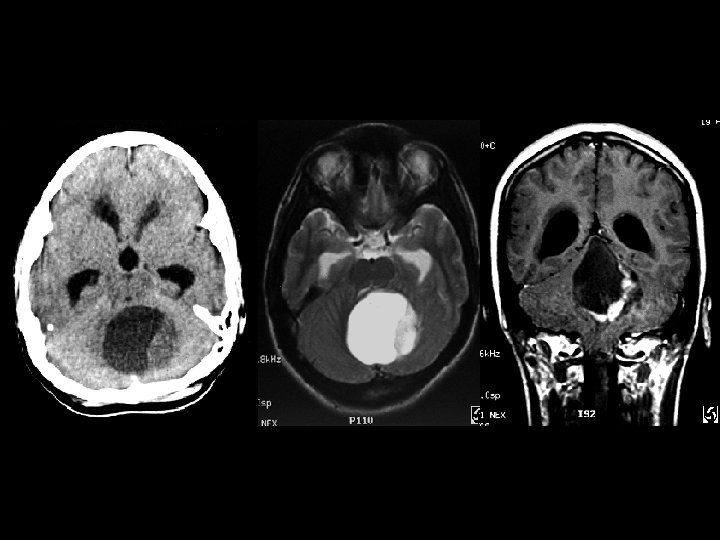

Juvenile Pilocytic Astrocytoma • Findings: – Cystic cerebellar lesion with enhancing mural nodule – Obstructive hydrochephalus • ddx: – Hemangioblastoma (in adults = think VHL)